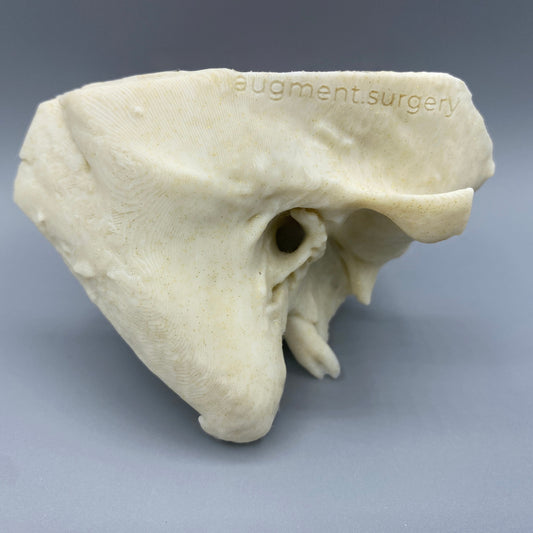

Plant-based surgical simulators made in the U.S.A.

Dissect each one to learn human temporal bone anatomy, hearing and vestibular systems.

Customize anatomy, colors, quantities, and more by contacting michelle@augment.surgery

Delta-Left OpenEar 3D Temporal Bones

Regular price $74.00 USDRegular priceUnit price per -

Delta-Right OpenEar 3D Temporal Bones

Regular price $74.00 USDRegular priceUnit price per -